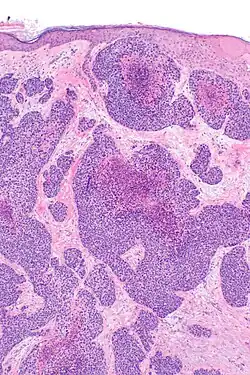

Histopathology

The microscopic histopathology of benign poroma tumors stained with hematoxylin and eosin dyes consists of poroid cells (i.e. small, round cells with oval nuclei and little cytoplasm) admixed with cuticular cells (i.e. epithelium-like cells) with centrally placed nuclei and abundant eosinophilic (i.e. colored pink or red due to uptake of the eosin stain) cytoplasm.[14] Porocarcinomas differ from poromas by their content of cells that are more irregular in size and contain misshaped nuclei[14] that often have conspicuous nucleoli.[15] Unlike the tumor cells in poromas, PCA tumor cells often appear to invade nearby normal tissues.[1] are rapidly proliferating as evidenced by their increased mitotic activity, and may have differentiated (this process is termed metaplasia) to appear as squamous cells, clear cells, mucous cells, or spindle cells.[11] PCA tissues may contain areas of necrosis (i.e. dead cells).[16]